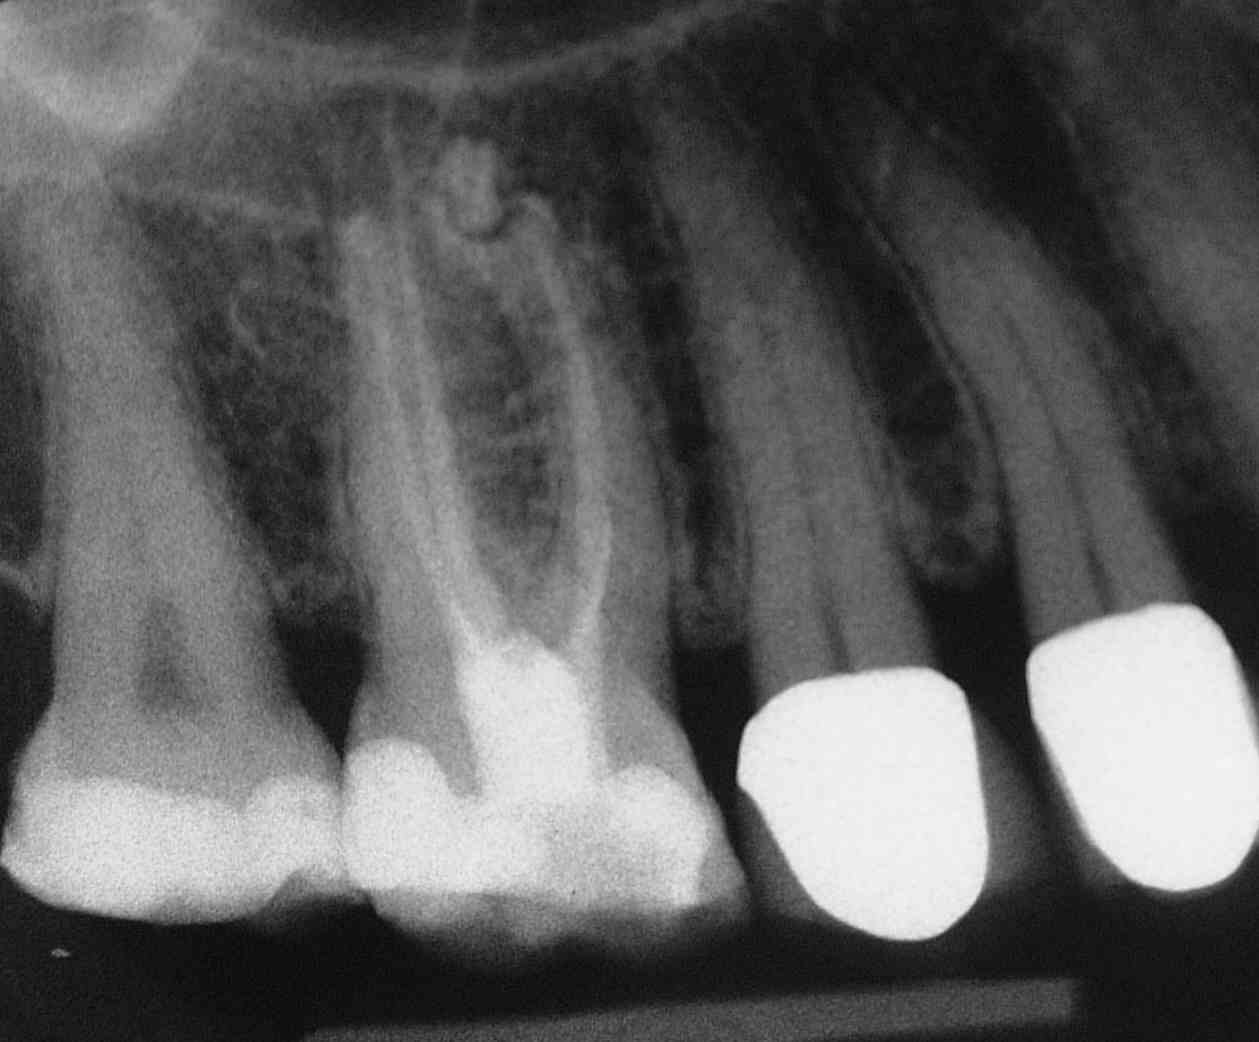

Im Gegenkiefer derselben Patientin ein endständiger Siebener mit Wurzelkaries und Verdacht auf Ausbildung einer apikalen Zyste. Der Mandibularkanal erscheint nach kaudal verdrängt. Nach “Apiken” der Aufhellung durch Überinstrumentieren mit einer 15er Feile entleert sich reichlich dunkles, blutig-seröses Exsudat, wodurch der Anfangsverdacht erhärtet wird. Daraufhin wird das Foramen apikale bis auf Isogröße 40 erweitert.

Im dritten Quadranten musste eine Revision wegen einer beschwerdefreien apikalen Ostitis durchgeführt werden (Zufallsbefund). Hier wurde selbstverständlich auch überinstrumentiert, jedoch lediglich ein wenig Sealer in den an einer Stelle erweiterten Parodontalspalt überpresst.